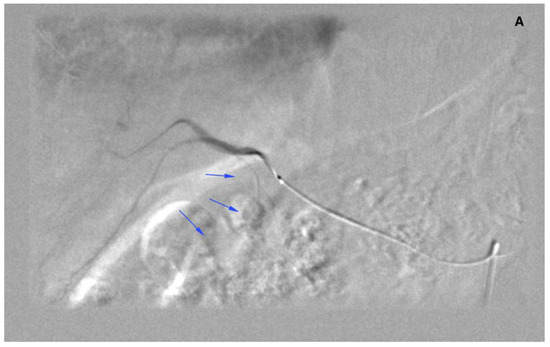

There were 20 patients after cholecystectomy. There were 30 (40%) patients with additional cystic arteries (Figure 3).

Figure 3.

Angiogram of the right hepatic artery. (A) Initially, single CA is visible (arrows) originating from the right hepatic artery division. (B) After embolization, another artery reveals multiple intrahepatic anastomoses to the gallbladder wall, and needs to be embolized. (C) There is insufficient embolization of both CA, and (D) retraction of the microcatheter reveals another CA originating proximally to the right hepatic artery division (arrows).